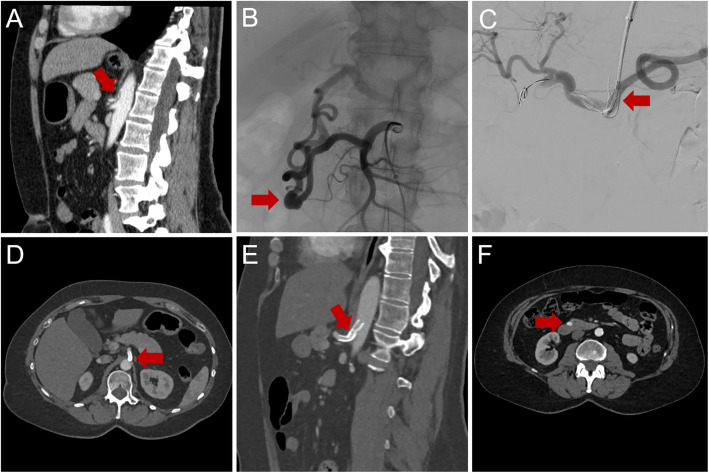

目的:确定胰腺周围动脉瘤(PPAs)中内脏动脉(VA)狭窄的频率和相关性,并为PPAs合并VA狭窄的情况制定统一、更详细的治疗策略,因为目前的指南没有充分解决这一问题。材料和方法:回顾性分析在三级医院诊断的PPAs患者。多发PPAs时,腹腔-肠系膜侧支循环内动脉瘤与血管比值(AVR)最高的动脉瘤为原发性动脉瘤,并根据器官缺血的危险性将其分为“危重”或“非危重”。腹腔动脉和肠系膜上动脉狭窄分级为低(50%)或完全闭塞。治疗策略基于VA狭窄的严重程度、动脉瘤的分类和形态。治疗策略包括血管内、手术和观察等待管理。结果:纳入PPAs患者31例,动脉瘤53个;平均动脉瘤大小:12.5±7.9 mm(范围5-38 mm), AVR: 3.5±2.1(范围1-11.3)。以胰十二指肠上、下动脉及拱廊为主(67.9%)。动脉瘤破裂组AVR明显高于动脉瘤破裂组(6.2±2.8;p = 0.031)。腹腔动脉狭窄占87.1%。动脉瘤大小与活动性出血的发生无相关性(p = 0.925)。11名患者出现了严重的动脉瘤,10名患者需要单独治疗。非危重性动脉瘤多数采用线圈栓塞治疗。结论:CA狭窄、动脉瘤位置和AVR显著影响治疗决策。PPA治疗需要基于解剖学和血流动力学因素的个体化方法。

Results: Thirty-one patients with PPAs were included with a total of 53 aneurysms; mean aneurysm size: 12.5 ± 7.9 mm (range 5-38 mm), AVR: 3.5 ± 2.1 (range 1-11.3). The superior and inferior pancreaticoduodenal arteries as well as the pancreaticoduodenal arcade were affected in most cases (67.9%). AVR was significantly higher in cases of aneurysm rupture (6.2 ± 2.8; p = 0.031). Celiac artery stenosis was present in 87.1%. Aneurysm size and occurrence of active bleeding did not correlate (p = 0.925). 11 patients presented with critical aneurysms, with 10 patients requiring individually tailored treatment. Non-critical aneurysms were treated with coil embolization in most cases.